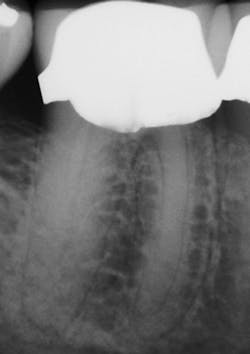

After preparing straight-line access to the canal orifice (figure 1), explore the canal using small-sized instruments. I typically use a size 08 SafeSider by hand with the help of an apex locator to determine working length. I then use the SafeSiders in sizes 10, 15, and 20 to verify patency and confirm a smooth, reproducible glide path (figure 2). I always irrigate and enlarge the glide path to a minimum 20/02 preparation.

Figure 2: Radiograph confirming glide-path creation using SafeSider instruments.